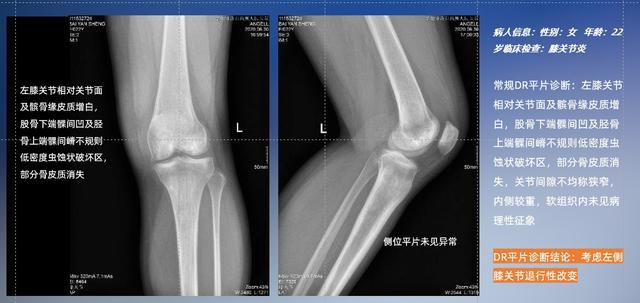

普通平片扫描与WR-3D扫描前后诊断结果对比

在负重位状态下,数字化X线三维扫描与重建,能够更好的呈现受检者关节受力改变的状态。德赢VWIN科技创新的WR-3D动态三维影像重建系统,通过数字化X线摄影完成三维扫描并重建三维影像信息,包括断层图像重建、MPR多平面重建、MIP重建以及VR体绘制。其扫描时间短,剂量相较于CT设备大幅缩减,同时成本更低,在临床诊断以及医疗方案制定中具有极大的价值意义。而相较于普通平片下的负重位扫描,负重位动态三维影像重建技术能够避免二维状态下的组织结构重叠、密度分辨率不足、组织解剖结构难以分辨等问题。WR-3D支持多角度的三维观察,能全面的呈现被检查部位在多个角度下的三维影像信息,极大的降低了二维负重位检查带来的漏诊率。